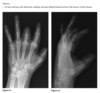

Anteroposterior view of the hands of a

patient with chronic renal failure shows subperi-

osteal resorption along the radial aspect of the

middle phalanges of the index and middle fingers

(Fig. 2.23.1, arrows). There are vascular clips from

a graft at the radial aspect of the right wrist (arrow-

heads). A lateral view of the skull in the same patient

(Fig. 2.23.2) shows a salt-and-pepper appearance.

Secondary hyperparathyroidism (HPT)

HPT is a general term referring to an

increased serum level of parathyroid hormone. Pri-

mary HPT results from an intrinsic abnormality in

the parathyroid gland (e.g., an adenoma, hyperpla-

sia, carcinoma). Secondary HPT is caused by a dif-

fuse, adenomatous hyperplasia, and tertiary HPT

develops from an autonomous parathyroid ade-

noma caused by the chronic overstimulation of hy-

perplastic glands in renal insufficiency.

Bone resorption along the radial aspect of

the middle phalanges of the hand (especially of the

second and third digits) is considered diagnostic of

this disorder.

Bone softening may lead to

basilar invagination, wedged vertebrae, bowing of long bones, and slipped capital femoral epiphyses.

Brown tumors, which are lytic, expansile lesions

that may mimic metastases or myeloma, occur in

the jaw, rib, and pelvis and are more commonly

seen in primary HPT. Osteosclerosis, more com-

monly seen in secondary HPT, is characterized by

bandlike sclerosis on the superior and inferior sur-

faces of the vertebral body (i.e., rugger-jersey spine;

Fig. 2.23.4). Soft-­ tissue calcifications can occur in

the viscera, cornea, periarticular regions, and hya-

line or fibrocartilage, causing chondrocalcinosis